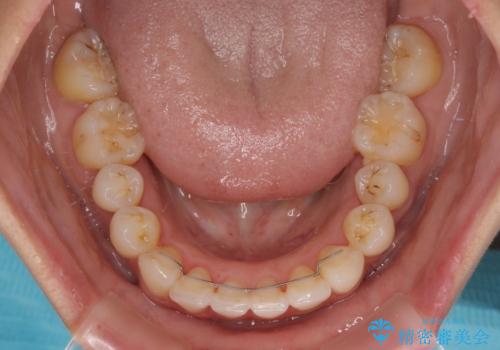

出っ歯になることなく、上下前歯が綺麗に接触する状態で仕上げることができました。